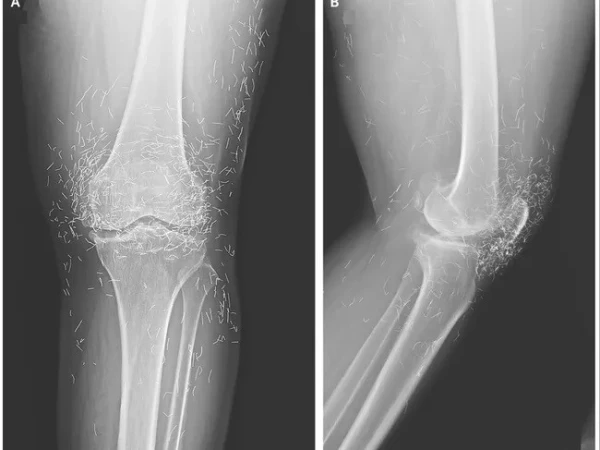

مذکورہ بالا تصویر ایک 65 سالہ خاتون کے گھُٹنے کے ایکسرے کی ہے جس میں دیکھا جا سکتا ہے کہ گھٹنے کے گرد سینکڑوں چھوٹے سونے کے تارموجود ہیں۔

بعد ازاں خواتین کے گھٹنے کا ایکس رے کیا گیا اور جو چیز سامنے آئی، وہ گھٹنے کے اندر سونے کے انتہائی باریک تار تھے۔ دراصل یہ تار اکیوپنکچر کے دوران باقاعدہ طریقے سے اندر چھوڑ دیے گئے تھے تاکہ جسمانی تحریکی اثر برقرار رہے۔